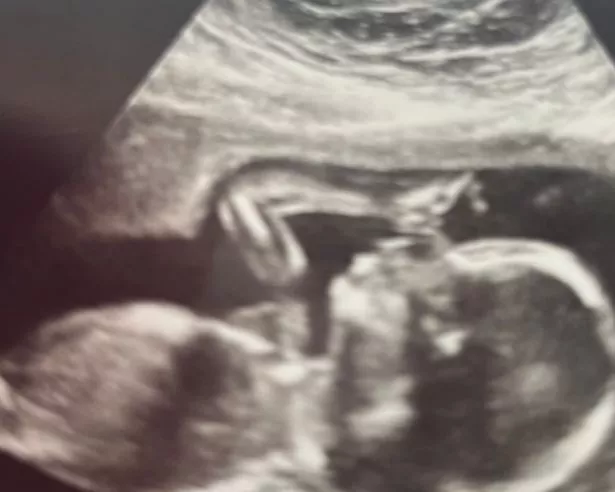

弗洛斯在子宫里的形象(图片:没有信用)